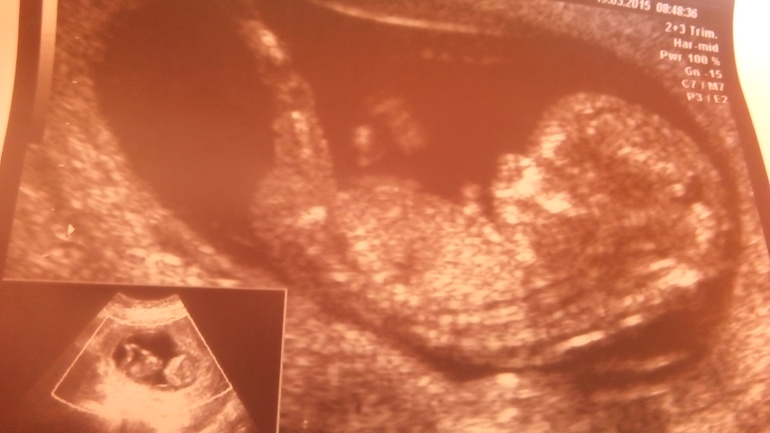

.тошнило меня кстати аж до 16 недель, ну до 20 еще иногда аукался. Кстати 14 февраля мы росписались😍. Второй скрининг показал что будет у нас сынок. Чувствовала я себя хорошо пуз рос как на дрожжах) до 30 недель можно сказать скакала. Потом потяжелее стало, кости мои болеть начали ну и отеки куда без них. В 32 недельки на узи напророчили нам крупного малыша. Стало страшно. Старший родился 3900. Роды были тяжелые. 11 лет назад. Но чем ближе подходил срок тем быстрее хотела родить, устала очень. Пробка отошла в 36 недель. В 38 недель зделали узи все хорошо, обвитя нет. На ктг схватки. В жк говорили не доношу. И вот прихожу я к ним в пдр, (22.09) сказать что они ох...и это ничего не сказать. Выписали направление в рд. и попрощались. В рд осмотр, ктг и дали еще недельку погулять. Начал болеть живот и поясница как на м. 23 начальсь выделения как в последний день м коричневые. 25.09 в 15 начальсь схватки легкие но с переодичностью сразу в 10 минут. Позвонила мужу. Он сразу и не поверил))) ждали ждали и всеравно както неожиданно. Я зная по первому опыту что процесс это не быстрый. Пошла в ванную. Привела себя в порядок. Полежала в водичке с часок. Вышла приготовила ужин. Схватки стали ощутимее через 7 минут. Но еще терпимые. Я себе спокойная как слон занимаюсь своими делами, а муж вокруг меня круги наворачивает. Может поехали уже? Страшно ему было) в 7 я здалась. Вызвали такси рд в 15 минутах. Приехали схватки уже раз в 5 мин. Осмотр 2 пальца 😲а я думала их там уже хотябы 5((( вердикт в род зал еще рано оформим мы тебя в патологию 2 часа погуляеш и переведем в род зал. Говорю не хочу я лучше с мужем 2 часа вокруг др погуляю. Не отпустили, мол мы тебя оформим а потом выходи еще время приемное можешь погулять. Поднялась на ктг. А потом не выпустили! Обманули гады) к 8 интервал был уже 2-3 мин. Было мне уже туго. Девочки в патологии явно перепугались). В род зал все не ведут. Оказалось он у них занят был. У нас были партнерские роды. В итоге попала я в родзал в 9 с открытием в 4 пальца и схватками через минуну по минуте вот это была уже жесть. Прошу эпидуралку минут через 20 пришел анастезиолог. Была уже одна сплошная схватка облегчения небыло совсем. Как ему удалось вколоть не знаю. Короче молодец дядя. Боль постепенно стала спадать и пропала совсем)) благодаря эа у меня пошло раскрытие. За 40 минут стало полное. Эа начала отпускать и пошли потуги. Вроде все получалось хорошо врач меня хвалила но голова застряла потуги пропали боль не реальная. И начали мы ее витуживать без потуг. Это пипец. Но мы справились))) в 10.20 положили мне на живот сынулю. 😍😍😍это счастье. И тут я вспомнила про мужа 😲мы про него забыли и я и врачи, пипец а он там внизу сидит нервничвет, что его так долго не зовут? Родили послед, зашили трещинку. Приходит муж комне а я ему на детский столик. Вы б его видели, недоверие восторг, че там только небыло. Дали ему сынулю на ручки так мы просидели 2 часа. Сынуля дрых. А мы были самые счастливые. Врачи и мед сестры замечательные рожали по прописке бесплатно. Потом поблагодарили конечно но чисто символически. Кто еще не родил всм легких родов в срок.